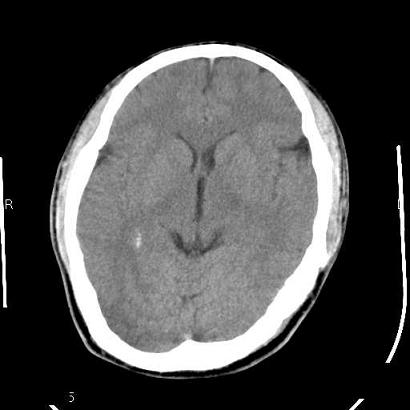

男,39岁,外伤来诊,老师们看看枕骨是什么病

枕内隆突左缘板障区示不规则囊状透亮区,颅骨内外板规整,无膨胀及缺损,周围无软组织肿块,考虑板障血管性病变,1.板障静脉湖,2.枕骨血管瘤(局部无膨胀性改变,无硬化环及钙斑影,故不太支持)。

蛛网膜颗粒压迹不会象这样有清晰的内板显示的!压迹压迹肯定是把内板压到板障里撒!各位老师同意不?